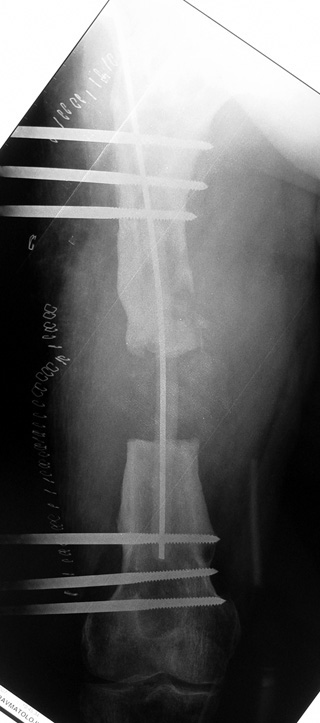

The duration of external fixation (external fixation index) depends on the amount of distraction required, and the extremity is prone to complications during this period. After the distraction phase is completed, the external fixator remains in place during the consolidation phase, which lasts twice as long as the distraction phase; but this period is hardly tolerated. If the external fixator is removed before sufficient consolidation is achieved, fractures, deformity and shortness will be the result. In our department, ‘lenghthening over nail’ method is used in order to decrease the external fixation index and increase patient comfort and activity level. In this method, the intramedullary nail is statically locked after the completion of the distraction phase, and external fixator is removed. The extremity is stabilized by the intramedullary nail during consolidation phase. In this way, complications due to long external fixation index or early removal of the external fixator are avoided.

Case 2